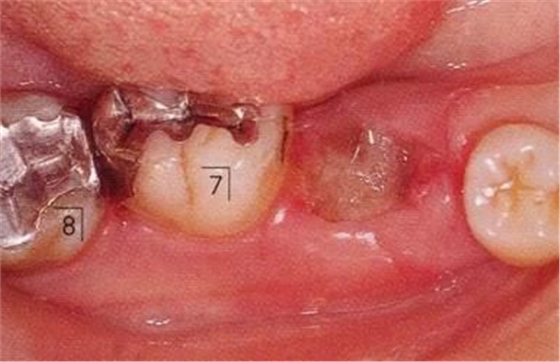

▲圖11-1,2

▲圖11-1,2 術(shù)前的X光片、右下6,7之間存在牙根接近,并存在10mm的牙周袋。

▲圖11-3,4

▲圖11-3,4 齦瓣剝離翻開(kāi)的狀態(tài)。右下6的遠(yuǎn)中牙根有較深的骨組織缺失,右下7的頰側(cè)有II度根分叉病變和近遠(yuǎn)中側(cè)有垂直型骨組織缺失。

▲圖11-5

右下6進(jìn)行牙半切除并將遠(yuǎn)中牙根拔除。右下5,7的骨組織缺損部位進(jìn)行骨組織移植,以及在右下7進(jìn)行GTR(wraparound)。

▲圖11-6,7

▲圖11-6 修復(fù)完全后6個(gè)月。

▲圖11-7 術(shù)后4年4個(gè)月。